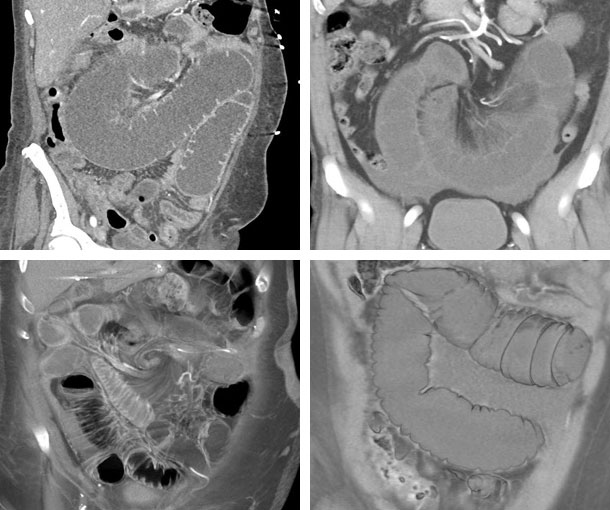

Midgut Volvulus CT Findings

- Swirling of bowel loops and vessels around the central SMA (“whirl” or “whirlpool” sign)

- Can cause SBO

- Can lead to ischemia and infarcted bowel if not treated